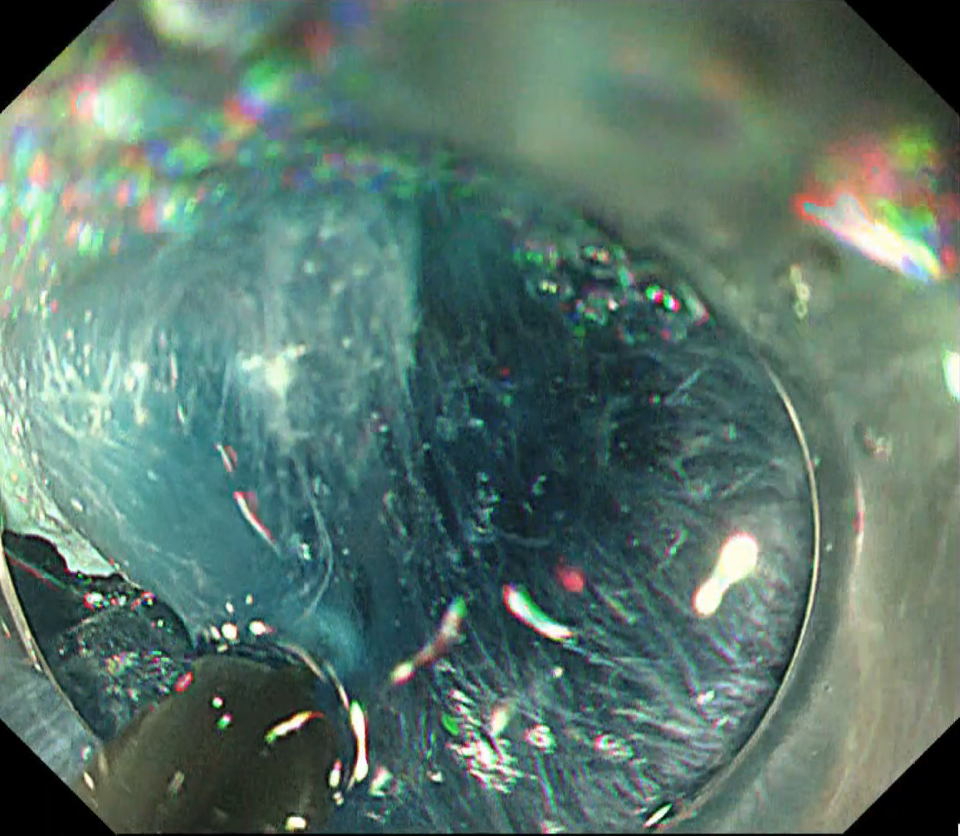

Once the flap was raised, clip-with-line traction was applied, and submucosal dissection was completed fairly quickly with the ITknife nano (Fig. 7, Movie 1). With traction in place, the theoretical risk of perforation approaches zero. Dissection is performed in coagulation mode, melting the tissue while keeping the white insulated back of the tip visible through the blue submucosa (Fig. 8).

Safety is enhanced by pushing the knife toward the lumen rather than pulling proximally.

Pull-cutting often slows the operator and leads to a shallow plane because of fear of damaging the muscle layer. Pushing the ITknife nano forward instead can produce surprisingly rapid

progress, the blunt tip tunnelling through the submucosa while maintaining a generous safety cushion.